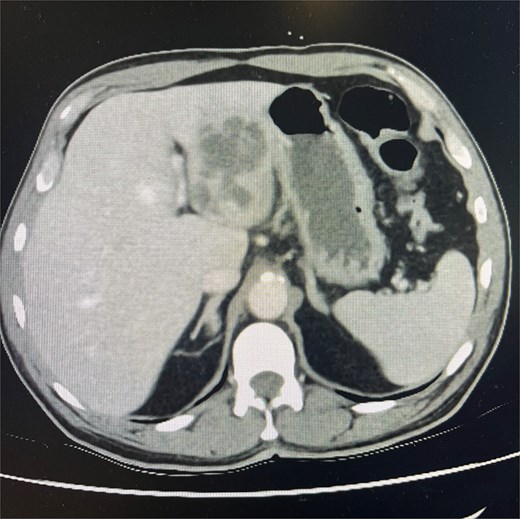

Cross-sectional imaging with ultrasound, computed tomography (CT) (Fig. 1), and magnetic resonance imaging (MRI) (Fig. 2) showed a rapidly-growing large, complex lesion measuring ~55 × 39 × 43 mm in the left hepatic lobe, with features suggestive of an evolving abscess but no drainable collection. Empiric IV piperacillin-tazobactam was commenced.

CT abdomen and pelvis in portal venous phase in axial slice. Hepatic abscess seen in left hepatic lobe.